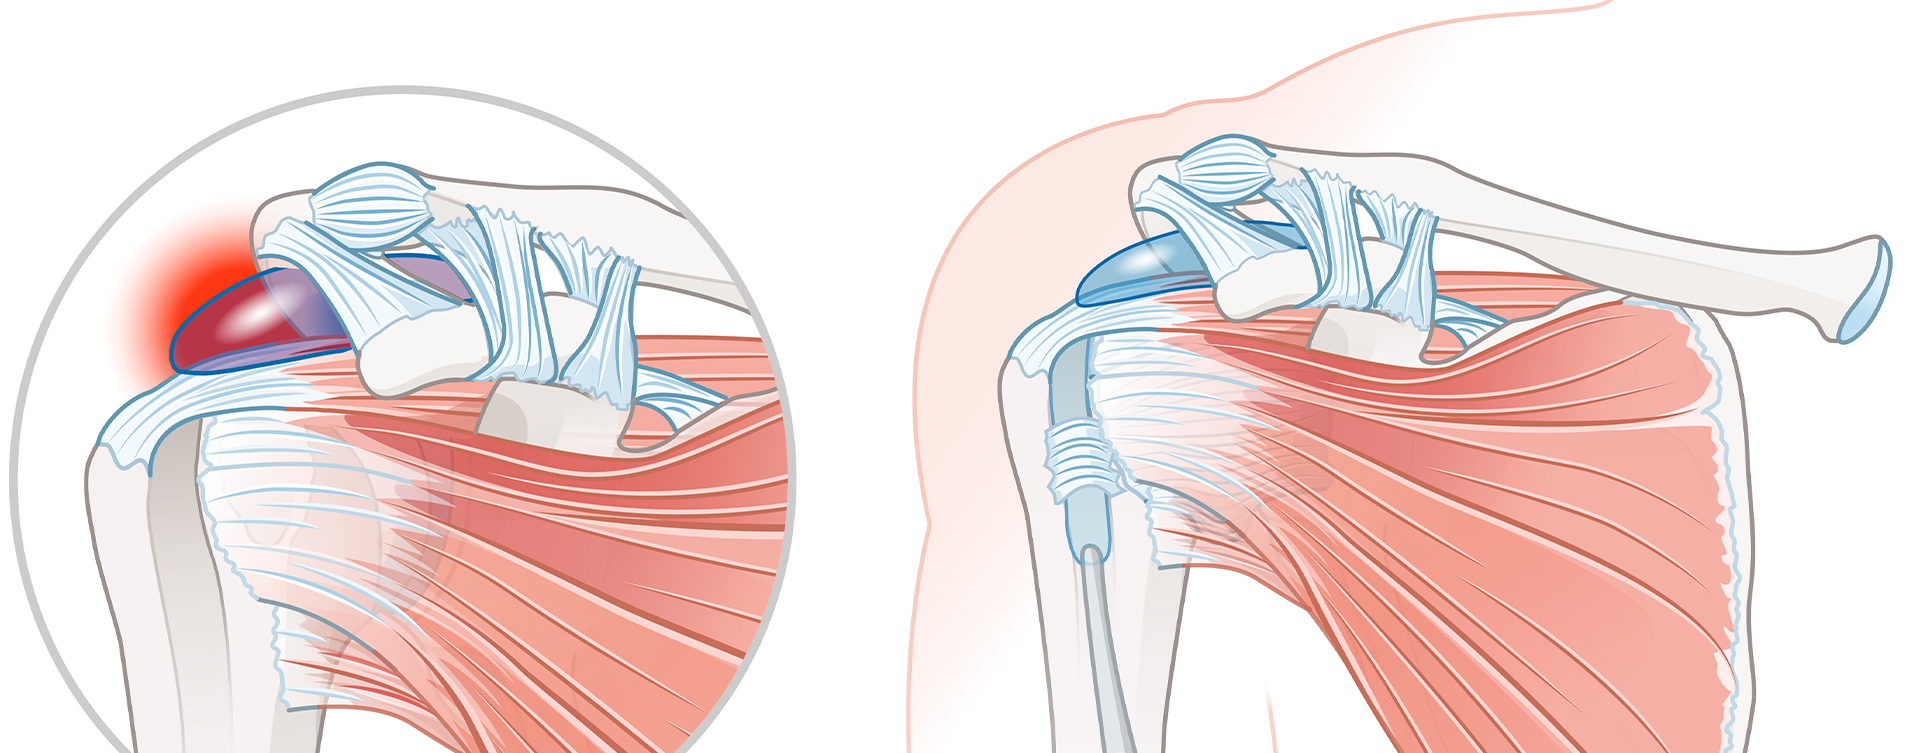

Bursite Subacromial

Bursite Subacromial

A bursite subacromial é a inflamação da bursa localizada entre o acrômio e os tendões do ombro. Provoca dor ao levantar o braço e pode estar associada à tendinite. Com tratamento precoce, envolvendo fisioterapia e medicação, é possível evitar a evolução para quadros crônicos de dor no ombro.

Síndrome do Impacto Subacromial

Síndrome do Impacto Subacromial

Essa condição ocorre quando os tendões e a bursa ficam comprimidos sob o acrômio, gerando dor e limitação nos movimentos acima da cabeça. É comum em atletas de arremesso e em trabalhadores com movimentos repetitivos. O tratamento inclui fisioterapia, ajustes posturais e, em casos graves, cirurgia por artroscopia.